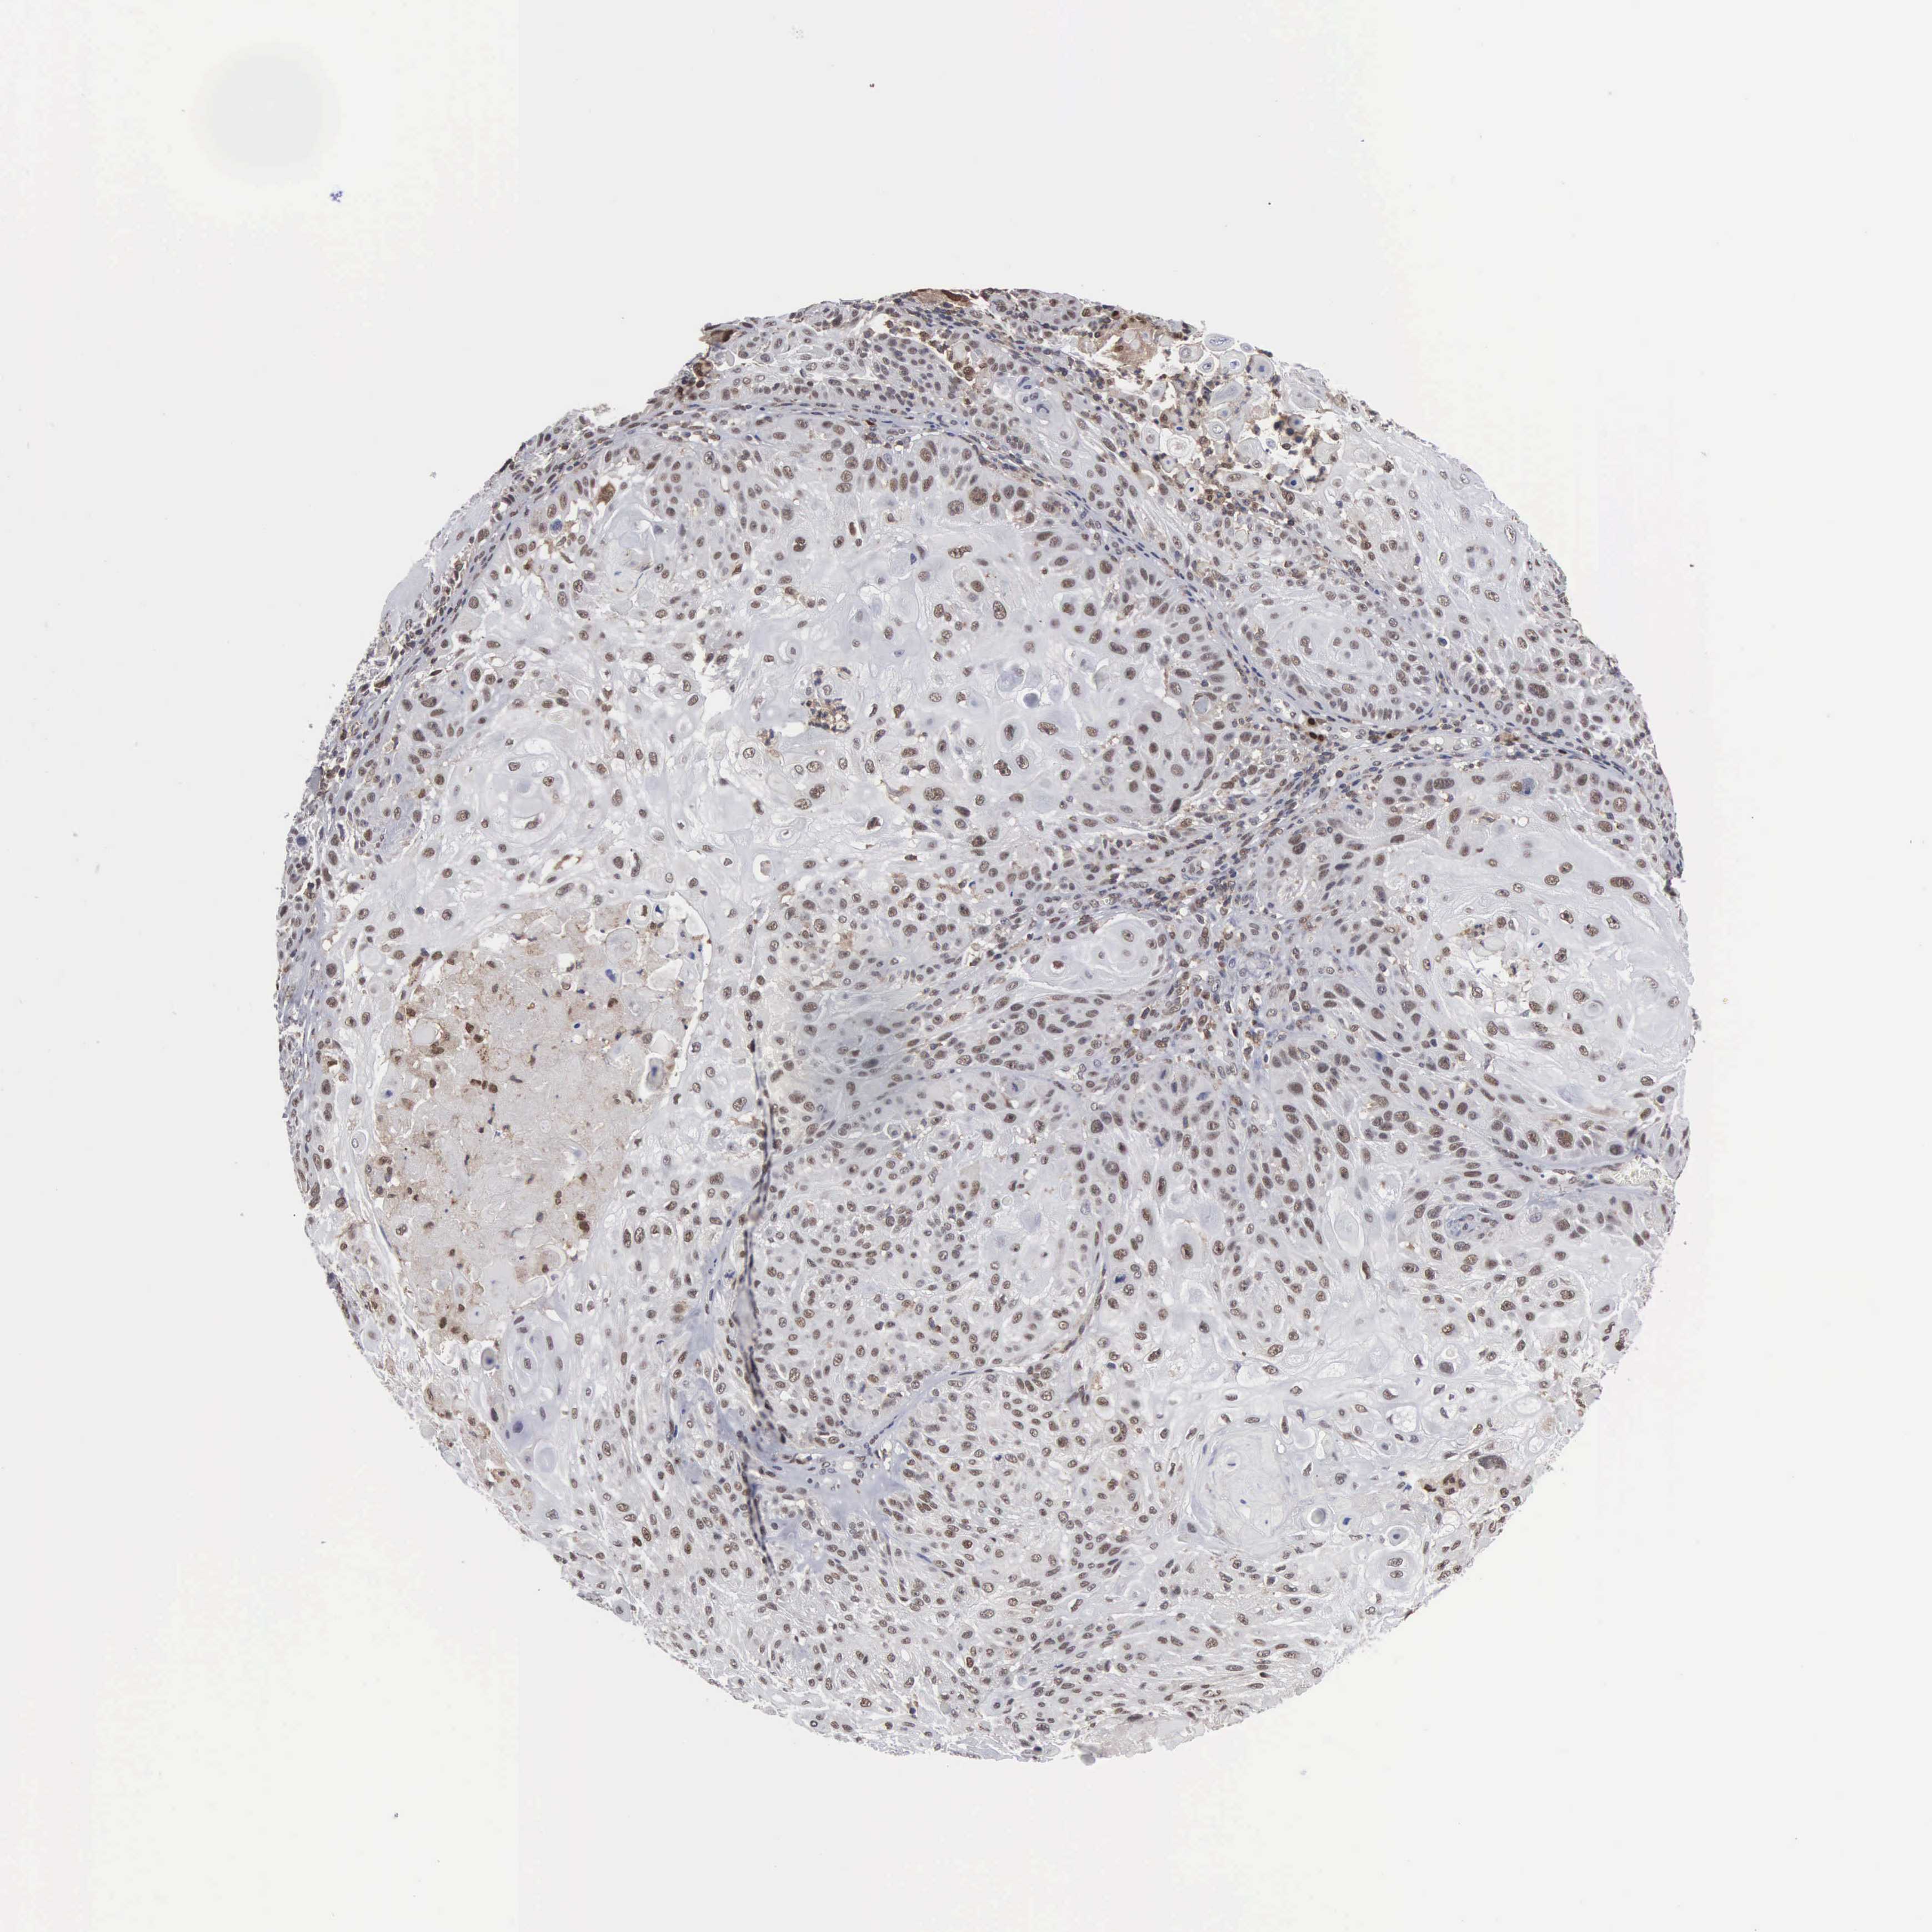

CANCER SKIN CANCER Show tissue menu

Basal cell and squamous cell cancer

SKIN CANCER - Protein expressioni

A mouse-over function shows sample information and annotation data. Click on an image to view it in a full screen mode. Samples can be filtered based on level of antibody staining by selecting one or several of the following categories: high, medium, low and not detected. The assay and annotation is described here.

Each image is clickable and will lead to virtual microscopy that enables deeper exploration of all samples and also displays staining intensity scores, fraction scores and subcellular localization as well as patient and tissue information for each sample.

Antibody HPA000943

Staining

High

Strong

Quantity

Location

Squamous cell carcinoma, NOS